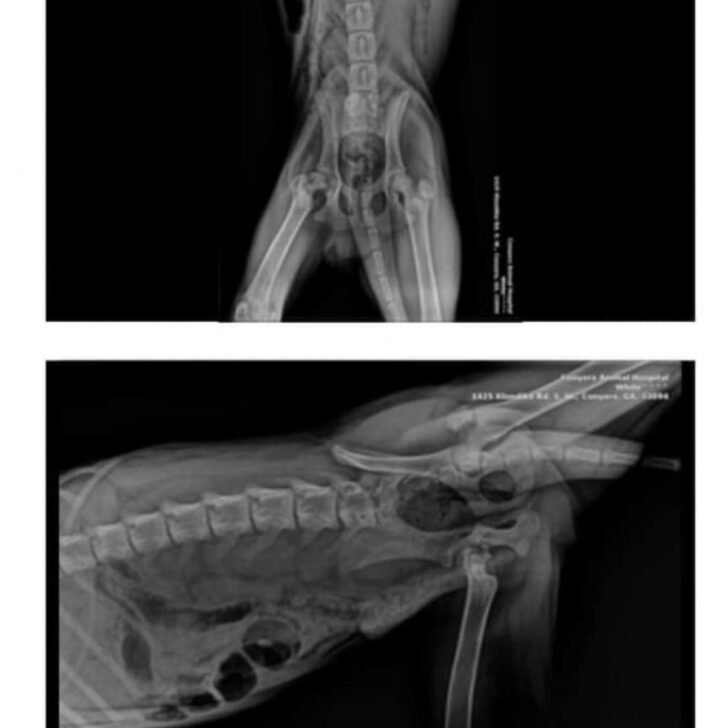

Sadly, Hank had to face many health issues and get ready for a long recovery. The vet results revealed his leg had been broken for over two weeks. Hank’s condition was so severe that the vets said his only chance to be pain-free was euthanasia.

Initially, they focused on helping Hank regain strength and receive the necessary nutrients so he could undergo surgery to repair his broken leg. Meanwhile, vets and shelter staff showered him with love to boost his spirits.

Thanks to the vets and shelter’s unwavering dedication, as well as donations, Hank successfully underwent his first surgery.